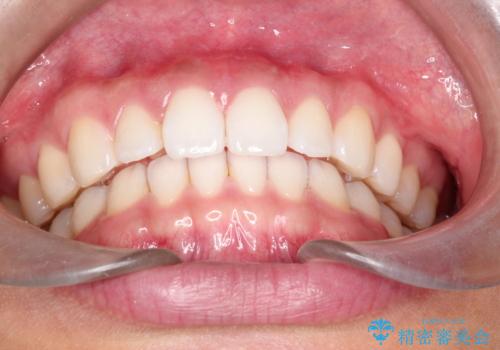

すきっ歯のインビザラインによる目立たない矯正

- すきっ歯を治したいとのことで来院されました。

上下ともに前歯に隙間がありました。

目立たない装置をご希望のためインビザラインで矯正治療を行うこととしました。

使用時間を守っていただけたので、スムーズに治療を終わることができました。